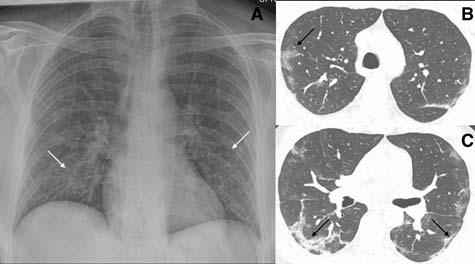

Fig 1 — CXR (A) and CT (B) images of a 45-year-old male who presented with fever and cough. He had hypoxia and leukopenia on examination and his nasal swab was positive for SARS COV-2. CXR shows bilateral blurred opacities with unclear vascular margins (white arrow) with corresponding ground glass changes in the CT (black arrows). Images reproduced with permission from Covid-19 Database of the SocietaItaliana di Radiologia Medica e Interventistica.